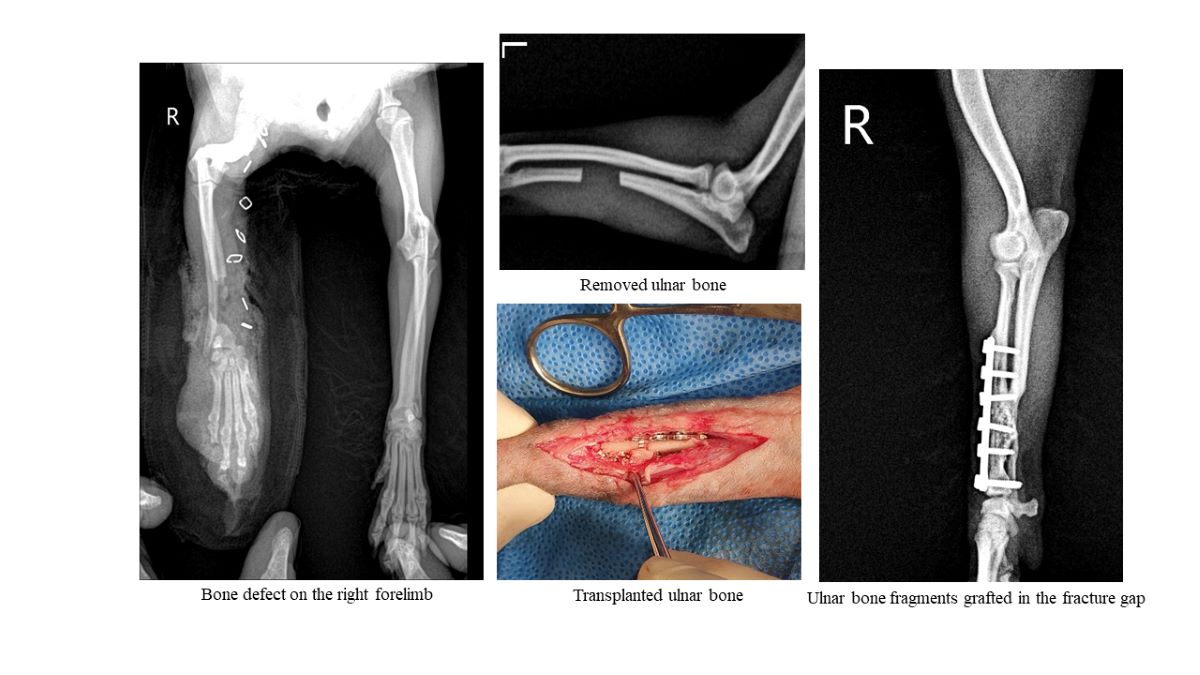

For autologous ulnar transplantation, 15 mm of the diaphysis of the ulna was collected through an incision in the middle of the left forearm using a sagittal saw (Stryker TPS System, Stryker, Kalamazoo, Michigan, United States) (Figure 3B and C). The collected ulnar bone was protected with gauze soaked in saline until transplantation. The incision in the left forearm was routinely sutured. A cranial lateral approach to the right forearm was used for the transplantation of the radius bone defect. The edge of the atrophied bone was arranged using a single bone rongeur (12 cm, Mabson Industry, Pakistan), and the bone marrow cavity was widened using a 1.2 mm K-wire (1.2 mm×229 mm, General Vet Products, Australia). A 1.5 mm titanium T-shaped plate (Radius Reduction Plate TH type, Doiff, Korea) was placed on the bone defect to check its size (Figure 4A), one 1.5 mm screw was inserted into the proximal radius bone, and the remaining 1.5 mm screws were inserted alternately into the collected ulnar bone and radius bone. It was inserted through the cortical bone opposite to the ulnar and radius bone (Figure 4B). Cancellous bone collected from the nonaffected humerus and BMP were transplanted at both ends of the fractured radius bone and around the ulnar bone fragments (Figure 4C). The muscles, subcutaneous tissue, and skin were routinely sutured.

Figure 2e shows that sugar promoted second intention healing, as a result of necrotic tissue removal and epithelialization on day 10 of the sugar therapy intervention. In this study, an autologous cortical bone fragment (15 mm in diameter) from the ulna was used as a graft and implanted into the midshaft of the contralateral missing radius. In dogs, the iliac crest, proximal humerus, and proximal tibia are considered the most plentiful sources of autologous cancellous bone [19].

Figure 3. Autogenous cancellous bone and ulnar bone collection. (A) Cancellous bone and bone morphogenic protein collected from the left humerus bone were mixed. (B) It was collected from the left ulnar bone. (C) In the radiograph, the removed ulnar bone was identified.

Figure 4. The operative process of transplanting a radius bone defect into the ulnar bone. (A) A T-shaped plate was used to determine the length and location of screw insertion. (B) Proximal radius bone fragments and the transplanted ulnar bone were positioned with a 1.5 mm screw. (C) A mixture of cancellous bone collected from the nonaffected humerus and BMP was transplanted around the ulnar cortical bone graft.